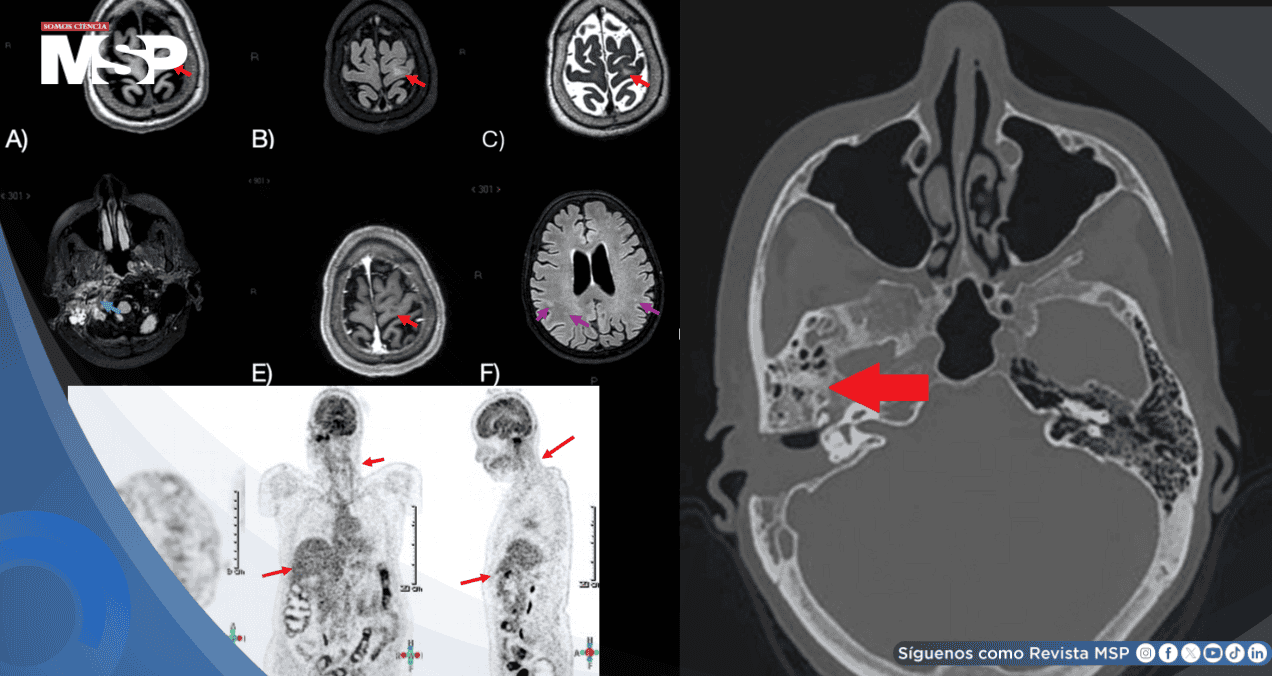

La tomografía contrastada mostró mastoiditis severa con destrucción ósea y absceso post-esternocledomastoideo. Se realizó drenaje quirúrgico, aislándose Pseudomonas aeruginosa en cultivos.

La resonancia magnética cerebral reveló lesiones hiperintensas en sustancia blanca subcortical y cambios inflamatorios en la fosa infratemporal. El PET-CT para descartar neoplasia no mostró captación anormal.

Considerando la mejoría clínica y el antecedente epidemiológico, se solicitó PCR para Borrelia burgdorferi, que resultó positiva. La serología mostró IgG positiva, confirmando neuroborreliosis de Lyme con coinfección por Pseudomonas.